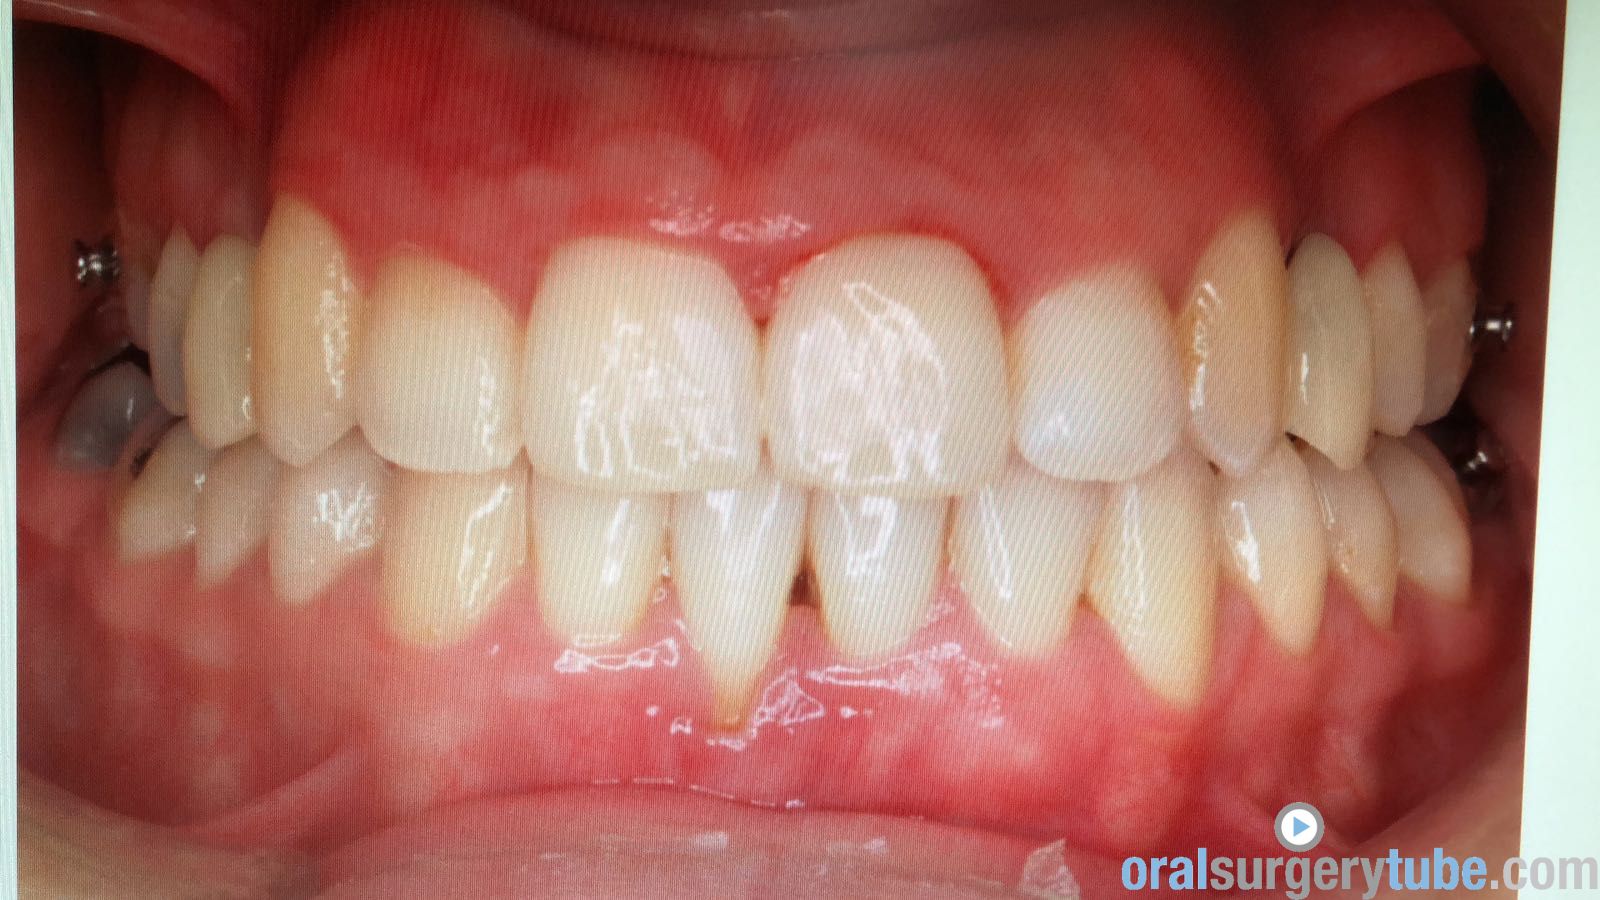

Paciente joven acude para consultar acerca de recesión gingival pieza 31 (clase II Miller). Paciente deja constancia de la importancia de la estética para ella. Hace unos 6 meses, se le realizó cirugía mucogingival con injerto conectivo palatino (la cuál fue fallida, ya que la recesión permanece)... Refiere además cierta molestia al traccionar del labio.

Al movilizar el labio, me transmite la sensación de haber quedado una inserción de fondo de vestíbulo alta... Pienso que podría ser debido a no haber realizado una desinserción muscular al reponer el colgajo coronalmente? (Foto 2). Considero que aún mantiene cierta cantidad de banda queratinizada, pero realmente mínima.

Dado a que se trataría de realizar una "reentrada" o retratamiento (no tengo experiencia hasta la fecha de haber tenido que retratar ningún caso de mucoginigval), agradecería toda opinión acerca de la técnica que más idónea consideréis... Teniendo en cuenta esas posibles adherencias musculares, el biotipo, la demanda estética de la paciente, no sé si lo ideal es tratar con injerto conectivo tipo "técnica bilaminar" y desinsertar la musculatura, o un Injerto de Encía Libre (FGG) y reponer apicalmente la musculatura...

La duda que me surge con el injerto conectivo es si el colgajo me permitiría ser reposicionado coronalmente, teniendo en cuenta esa sensación de "tirantez" actual que describe el paciente. Y la duda de realizarlo con FGG es si conseguiría cubrir la recesión por completo, y si es adecuado para ese solo diente...